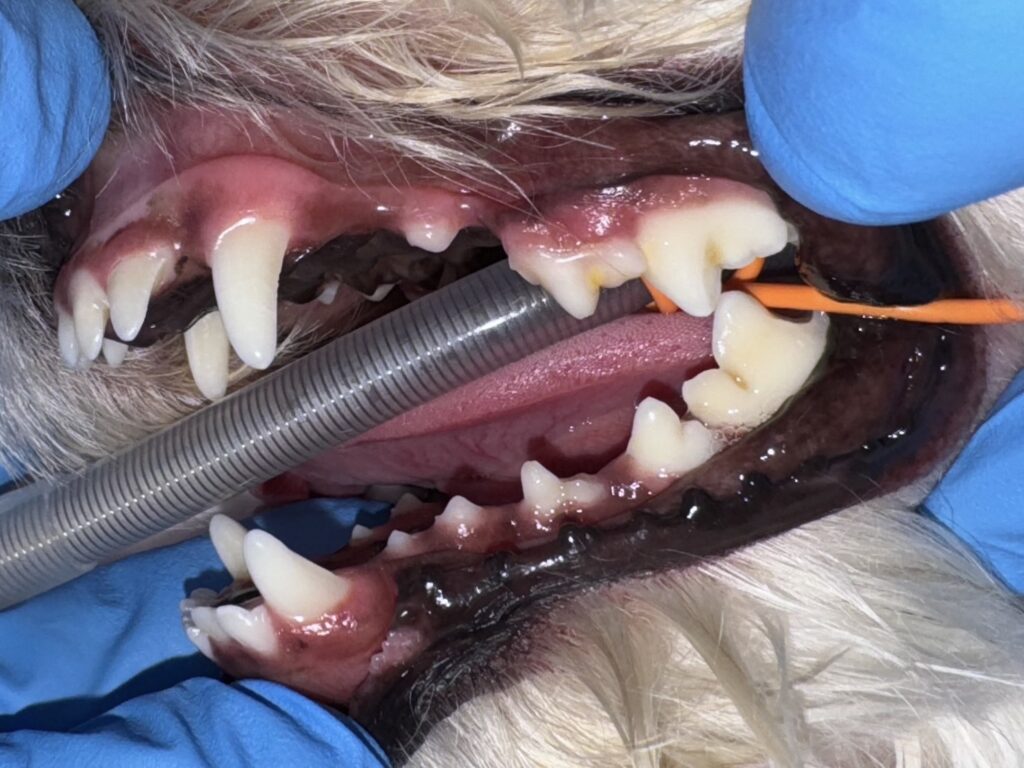

・Before

全身麻酔下で歯科検診・歯科レントゲン検査を行ない、

右第4前臼歯破折(歯肉縁下まで)

・象牙質露出

・乳歯遺残

・欠損歯

・歯肉炎軽度

が認められました。